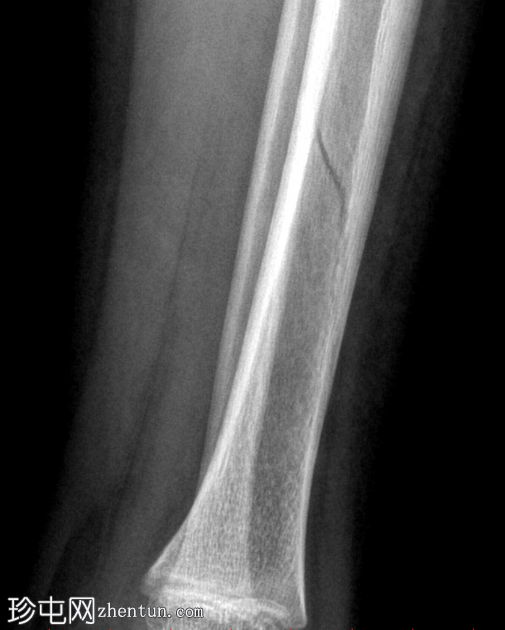

左腿及踝关节

X线片

正位

胫骨远端骨干可见一条螺旋状透亮线,提示骨折(正位、侧位)。

应用锐化算法并放大正位片(骨折由近端向远端)和侧位片。

幼儿骨折是指幼儿因扭转(足部着地时股骨内旋)导致的胫骨中远端轻微移位的螺旋状骨折,这种情况可能发生在儿童绊倒时。患者接受了6周的石膏外固定治疗。

请注意,应用锐化骨算法并放大图像后,骨折及其范围会更加清晰可见。